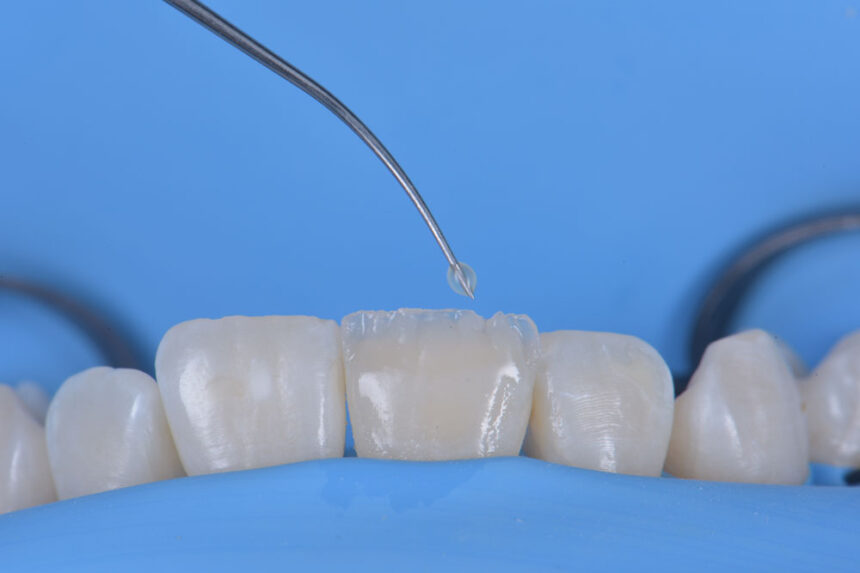

Στην εποχή της συγκολλούμενης αποκαταστατικής οδοντιατρικής ο έλεγχος της υγρασίας στο πεδίο εργασίας αποτελεί σημαντικό παράγοντα στην επιτυχία της τελικής θεραπείας. Ο οδοντίατρος καλείται να εκτελέσει σύγχρονα πρωτόκολλα διατηρώντας περισσότερη οδοντική ουσία και δημιουργώντας αποκαταστάσεις με μεγαλύτερη μακροβιότητα.

Στο σεμινάριο αυτό θα γίνει ανάλυση όλων των προτεινόμενων τεχνικών για την εφαρμογή της ελαστικής απομόνωσης σε άμεσες θεραπείες, σε συγκόλληση έμμεσων αποκαταστάσεων, σε συνθήκες επαναπροσδιορισμού του αυχενικού ορίου, στην εφαρμογή της σε περιστατικά ενδοδοντικών διαδικασιών., καθώς και στη χρήση αυτής σε ψηφιακή αποτύπωση. Αφού αναλυθεί ο κύριος εξοπλισμός και παρουσιαστούν οι αντίστοιχες προσεγγίσεις, ιδιαίτερη σημασία θα δοθεί στο πρακτικό μέρος της εξάσκησης των συμμετεχόντων σε σενάρια που προκύπτουν στην καθημερινή κλινική πράξη.